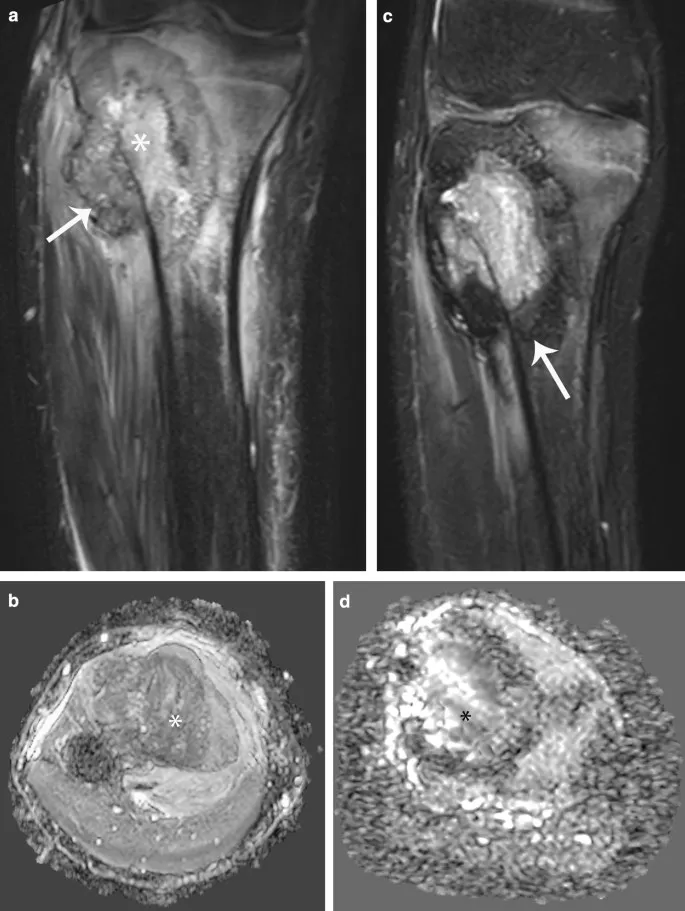

MRI characteristics provide tissue-specific information crucial for surgical planning and differential diagnosis. T1-weighted sequences demonstrate anatomical detail and marrow involvement, while T2-weighted and STIR sequences highlight edema, necrosis, and soft tissue extension.

| Tumor Type | T1 Signal | T2 Signal | Enhancement | Key Features |

|---|---|---|---|---|

| Osteosarcoma | Low/mixed | High/mixed | Heterogeneous | Bone/osteoid matrix |

| Chondrosarcoma | Low | Very high | Peripheral | Chondroid matrix |

| Ewing's | Low | High | Homogeneous | Extensive edema |

| Giant Cell | Low | Low/high | Intense | Hemosiderin deposits |

| Lipoma | High T1 | Intermediate | Minimal | Fat suppression |